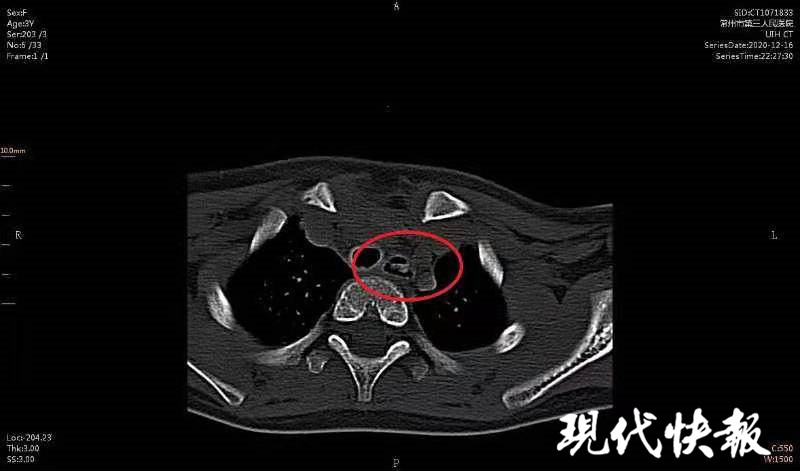

△CT顯示女童食道內(nèi)有異物

醫(yī)生檢查發(fā)現(xiàn),異物就卡在歡歡的食道里。“食道并不是一根直直的管道,它是有狹窄部位的,其中最容易引起異物嵌頓的狹窄有3處,處處都很危險(xiǎn)的。第1處狹窄位于食管的起端,是咽與食管的交接處;第2處狹窄在食管入口以下7厘米處,位于左主支氣管后方與之交叉處;第3處狹窄是食管通過膈肌的裂孔處。”常州三院耳鼻咽喉科副主任醫(yī)師陸曉宇說。